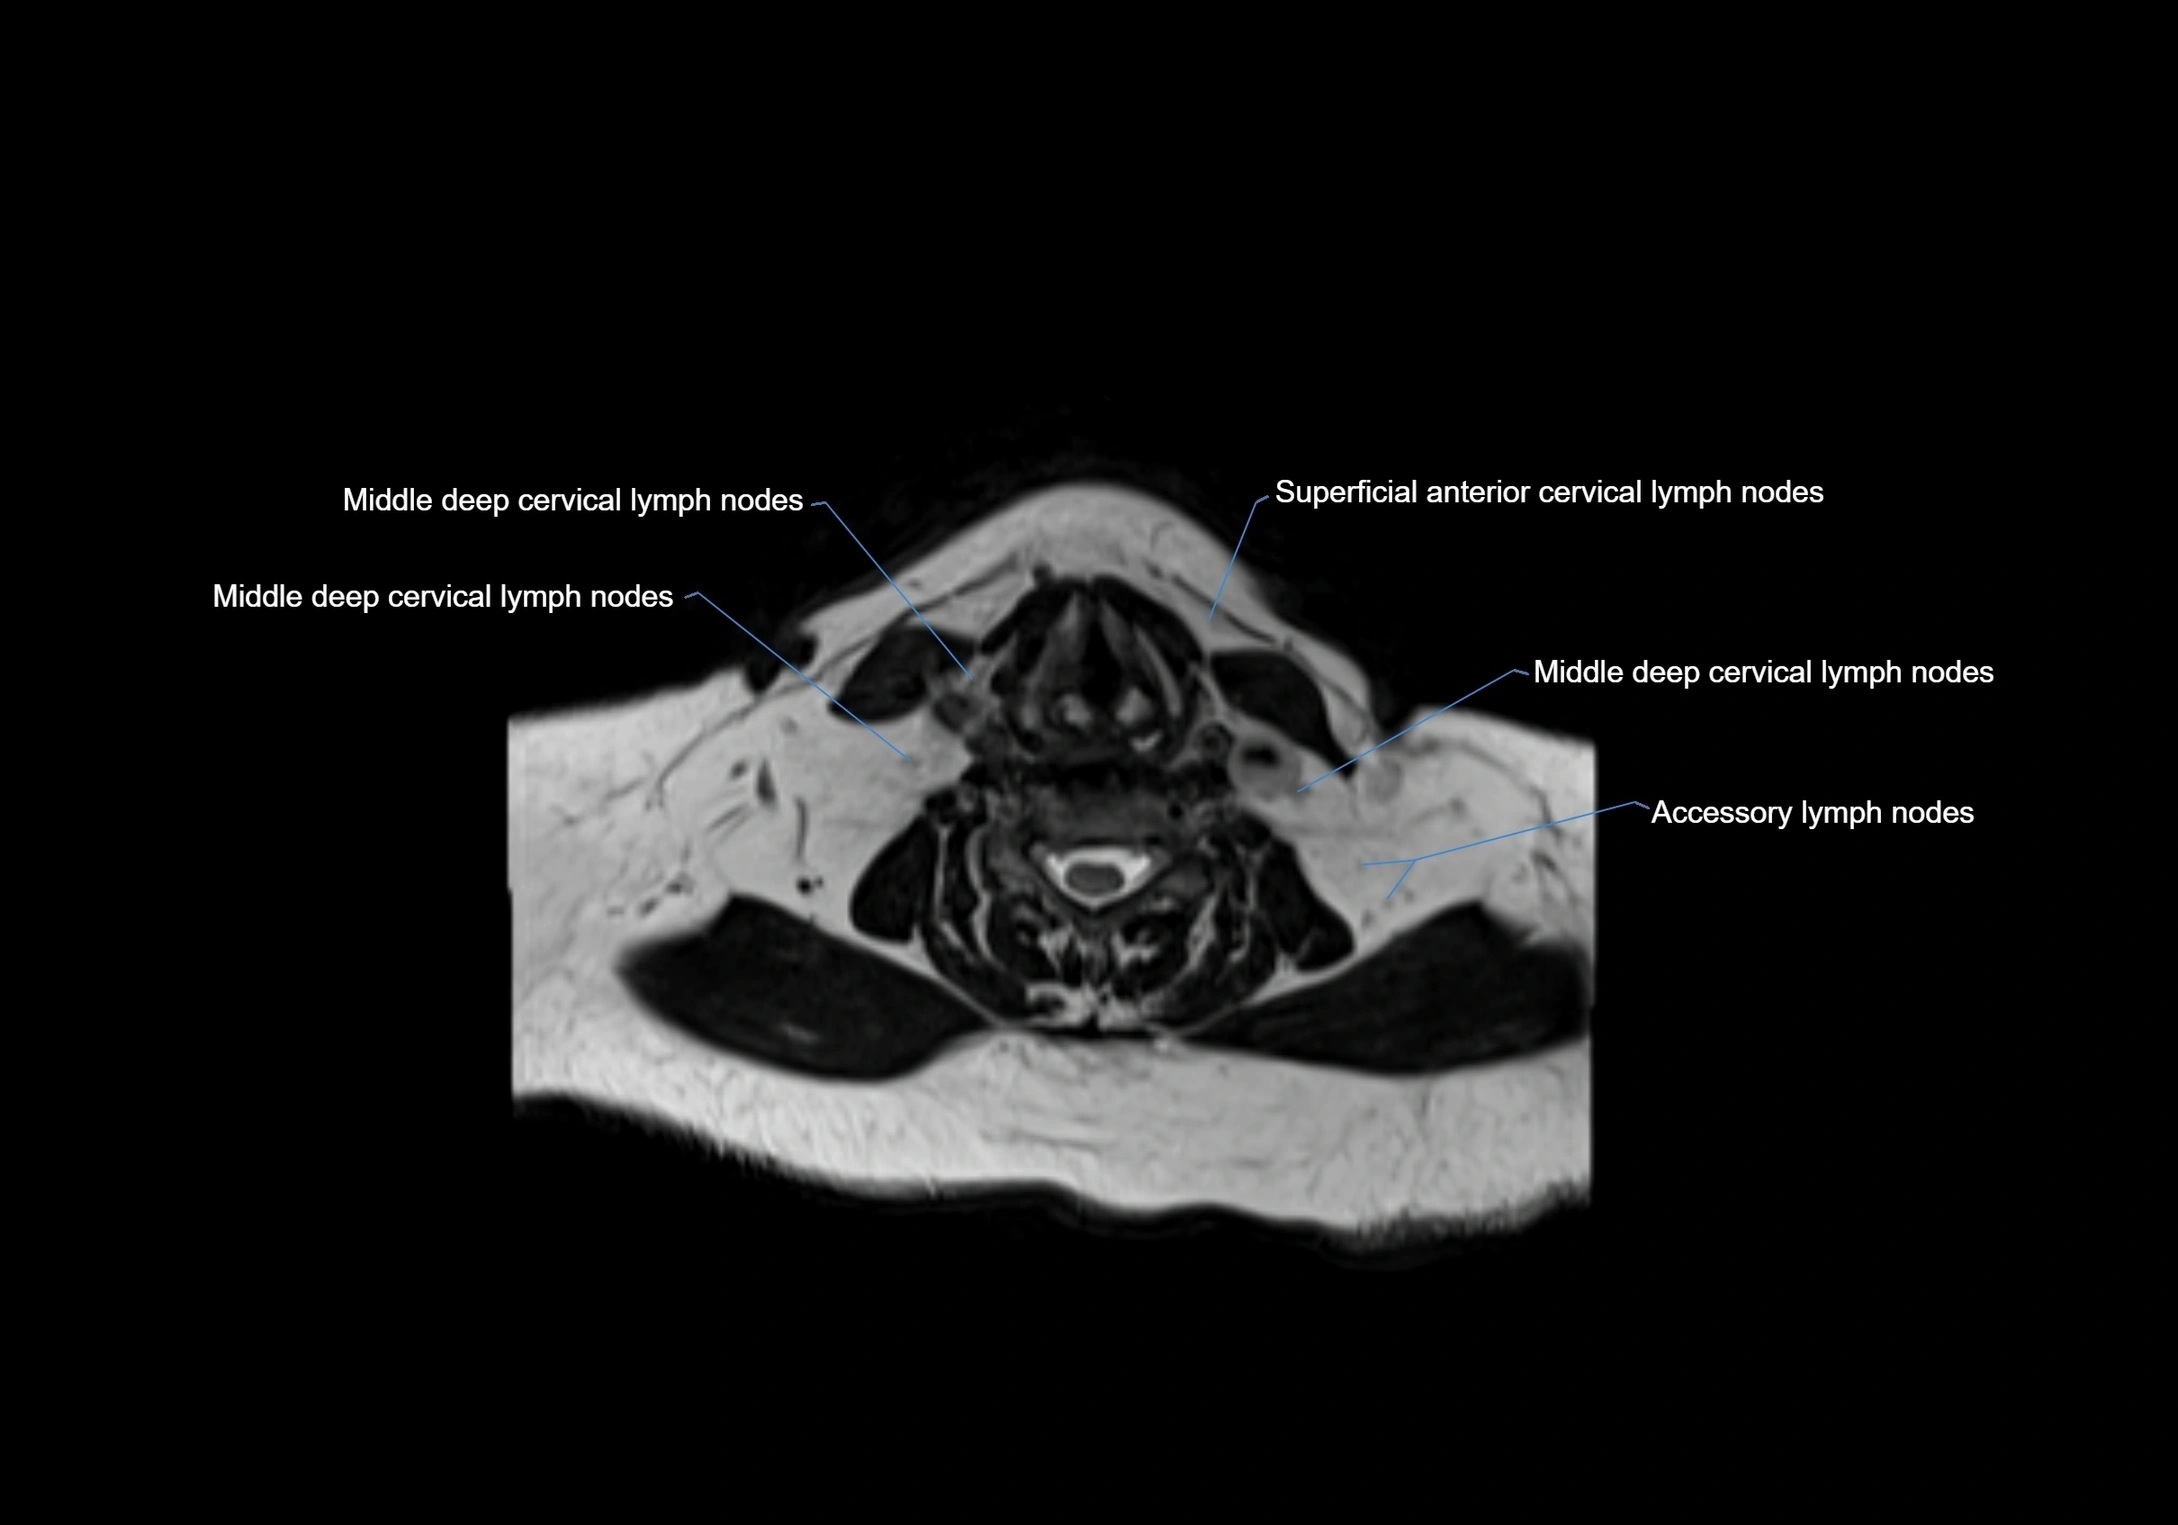

MRI Appearance

T1-weighted images:

• Normal accessory nodes appear as small, oval hypointense to intermediate signal structures within subcutaneous fat

• Surrounded by hyperintense fat, enhancing contrast for visualization

• Pathological nodes may appear enlarged or rounded, sometimes with cortical thickening

T2-weighted images:

• Nodes show intermediate signal, with surrounding fat bright

• Useful for detecting edema, inflammation, or infiltration

• Fatty hilum may appear slightly hyperintense relative to cortex

MRI images

image